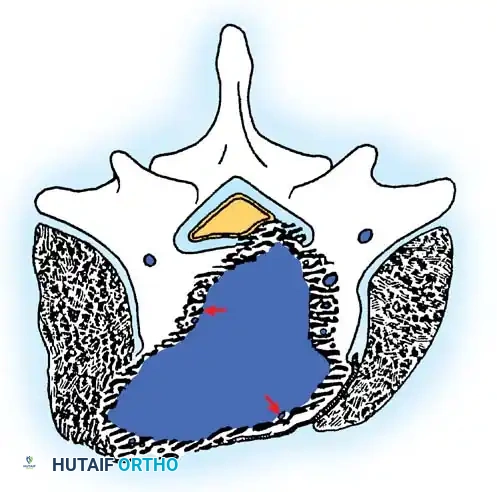

Stage 2: Active Tumors

Stage 2 tumors (e.g., osteoid osteoma, standard osteoblastoma, aneurysmal bone cysts) grow slowly and cause symptoms, usually pain or deformity. They possess a reactive pseudocapsule. Treatment usually involves en bloc excision where anatomically feasible, though meticulous intralesional excision combined with local adjuvants (liquid nitrogen, phenol, or polymethylmethacrylate [PMMA]) often suffices.

Cross-sectional representation demonstrating the expansion of an active Stage 2 benign lesion within the vertebral body, respecting the outer cortical margins but requiring meticulous intralesional clearance.